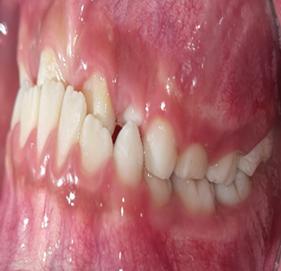

1. Carpio-Deheza G. Manual de instrucciones para la presentación de protocolos y monografías de diplomados, protocolos y tesis de espcialidad clínica/ quirúrgica, tesis de maestrías y doctorados en salud. Cochabamba: Universidad Mayor de San Simon, Facultad de Medicina Dr. Aurelio Melean, post grado UMSS; 2019.

2. Patrias K. Citing Medicine; The NLM Style Guide for Authors, Editors, and Publishers. [Online].: Bethesda (MD): National Library of Medicine (US); 2007 [cited 2022 marzo 29. Available from: https://www.ncbi.nlm.nih.gov/books/NBK7256/.